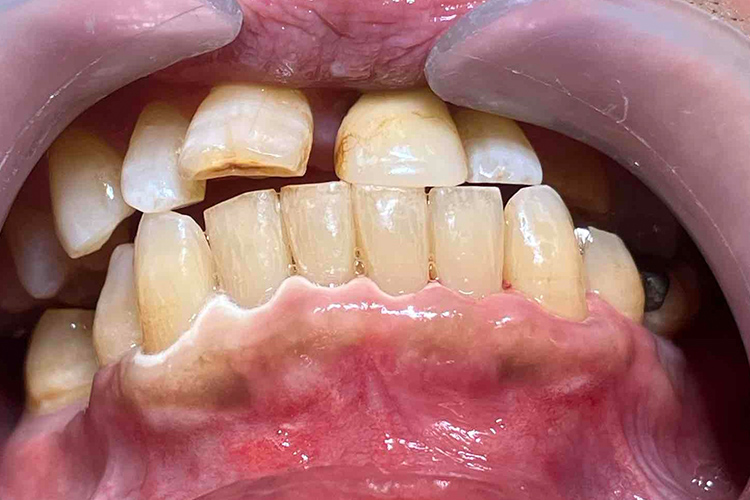

この患者様は、口腔内全体において重度の歯周病が生じており、歯磨き指導、クリーニング、Flap手術等を行ったが、歯周ポケットが深すぎるためブルーラジカル適用症例と診断し、施術を行いました。

施術前のレントゲンと口腔内写真です。施術前にプラークの除去を行ってから、施術します。